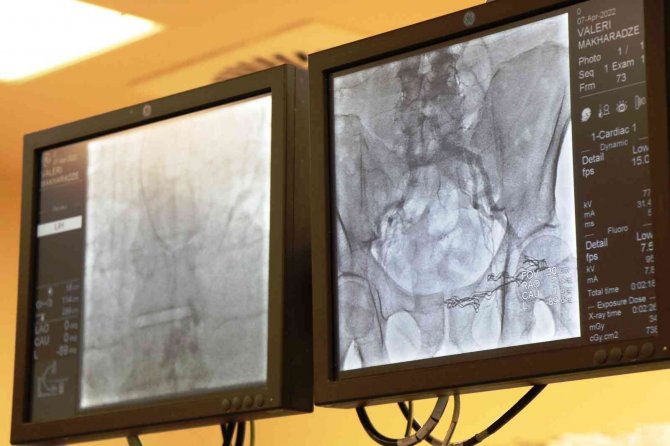

Gürcistan vatandaşı Valeri Makharadze, nefes darlığı ve çabuk yorulma şikayeti ile ülkesinde başvurduğu hastanede aort darlığı (kalpten çıkan ve vücuda kan taşıyan en büyük atar damar olan aortanın kapakçığındaki darlık) tanısı konuldu. Tedavi altına alındığı hastanede durumu kötüye giden Valeri Makharadze'nin ailesi uzun süre yoğun bakımda kalan Valeri'yi tedavi ettirmek üzere Samsun'a getirdi. Medicana İnternational Samsun Hastanesi'nde Kardiyoloji Uzmanı Prof. Dr. Korhan Soylu tarafından ameliyatsız kalp kapağı değişimi (TAVI) işlemi yapılan Valeri Makharadze, başarılı geçen işlemin ardından sağlığına kavuştu.

Valeri Makharadze'nin Samsun'da yapılan işlem ile sağlığına kavuştuğunu ifade eden Kardiyoloji Uzmanı Prof. Dr. Korhan Soylu, "66 yaşındaki Gürcistan vatandaşı Valeri Makharadze'de TAVİ işlemini gerçekleştirdik. Valeri, özel bir hasta. Gürcistan'da uzun süre yoğun bakımda kalıp, rahatlayamayan bir hastaydı. Ailesi bizlere başvurdu ve biz de kasıktan girerek daralmış ve yapıca bozulmuş aort kapağının yerine yeni bir kapak imlante ettik. İşlemimiz çok güzel oldu ve hastamızın hızlı bir şekilde normal hayatına döneceğini düşünüyoruz" dedi.

TAVI işlemi hakkında bilgi veren Prof. Dr. Korhan Soylu, "Transkateter aort kapak replasmanı (TAVI) işlemi, ileri aort darlığı olan hastalarda uygulanan bir yöntem. İlerleyen yaş ile birlikte aort kapağındaki kireçlenme, kapağın hareket kabiliyetinin azalmasına ve daralmasına yol açıyor. O yüzden de hastaların büyük kısmı 80 yaş ve üzerinde. Maalesef ilaç tedavisi ile de bu kireçlenme çözülemiyor. Bu nedenle de eskiden tek seçenek açık kalp ameliyatıyla kapağın değiştirilmesiydi. Günümüzde ise TAVI adını verdiğimiz ve aynı anjiyodakine benzer bir yöntemle bu kapak değişimi yapılabiliyor. Biz de uzun zamandır bu işlemi başarılı bir şekilde yapıyoruz" diye konuştu.